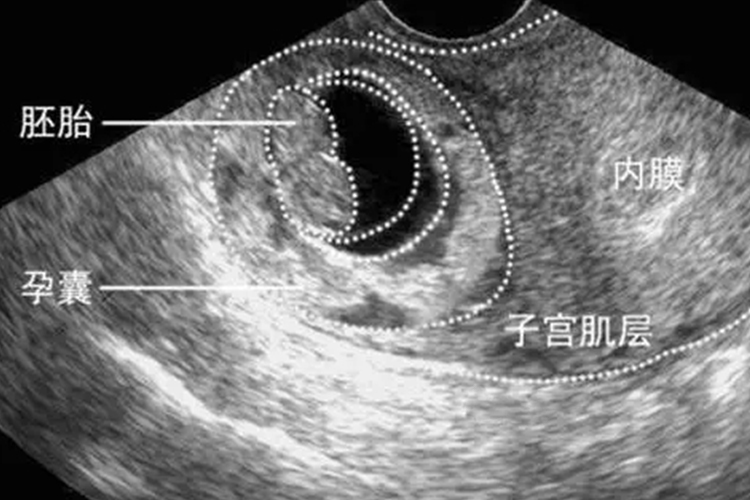

试管囊胚移植是试管婴儿技术中的一个重要环节,囊胚是胚胎发育的一个阶段,通常在受精后的5-6天形成。与早期胚胎相比,囊胚具有更稳定的结构和更高的发育潜能。在试管婴儿过程中,选择囊胚进行移植具有一定的优势。

在进行囊胚移植前,患者需要进行一系列的准备工作,包括子宫内膜的准备,通过激素调节使子宫内膜达到适合囊胚着床的状态。医生会对囊胚进行评估,选择质量最佳的囊胚进行移植。